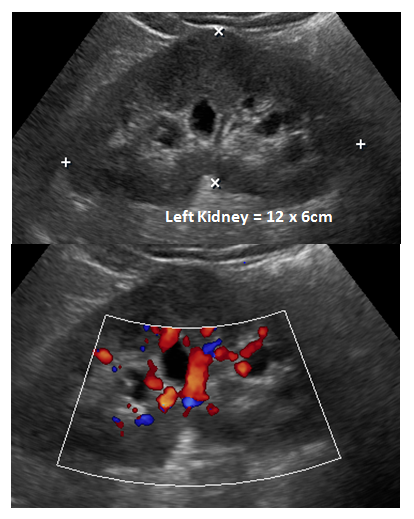

49yr old male patient with left loin pain. Patient referred for Renal Ultrasound for evaluation of urinary stone and obstruction. Renal Ultrasound reveals: Left mild hydro nephrosis. Renal pelvic was not demonstrated. No stone. No hydro ureter (Figure 1). Non-contrast CT recommended after as Ultrasound reveal left hydro nephrosis and failed demonstrating stone.

Figure 1 Renal ultrasound recommended ruling out urinary stone. Ultrasound demonstrates left mild hydro nephrosis. Renal pelvic was not demonstrated. No stone. No hydro ureter.